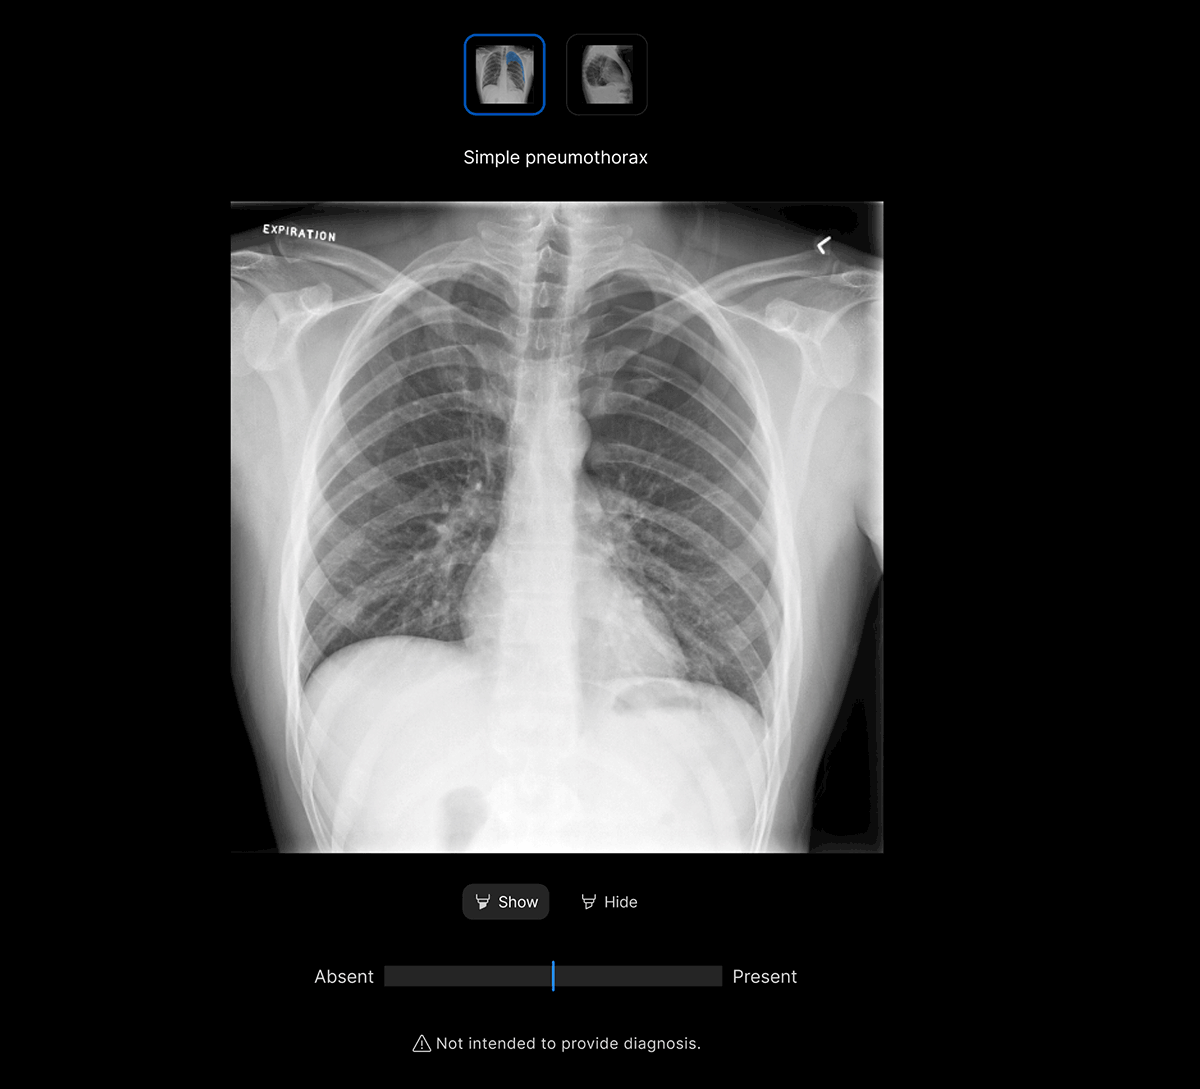

The user-interface integrates seamlessly with PACS/ RIS, displaying a resizable, no-click overlay window with findings and localisation.

Customisable thresholds for individual findings (to optimise for sensitivity / specificity), to tailor the workflow to your clinical setting or population.

- Explainable AI features such as localisation and a confidence bar to improve AI interpretability and clinical decision making.